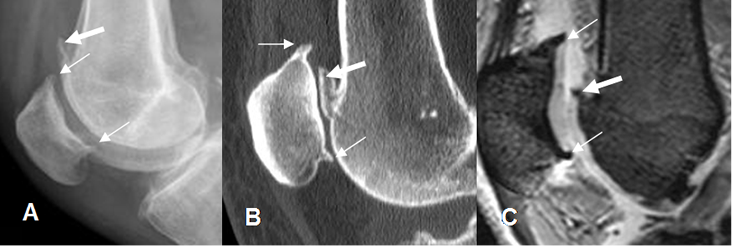

Fig 199. Artropatía degenerativa.

A: Rx lateral, B: TAC reconstrucción sagital y C: RM sagital en FFE. Presencia de osteofitos en el polo superior e inferior de la patela (Flechas delgadas) y la parte anterior del fémur distal. (Flecha gruesa).